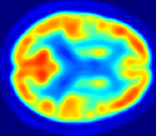

4.0.2 Qualitative Results

Looking at sample synthetic PET images in Fig. 3, it can be seen that all of the models are able to make reasonable predictions. The outputs of the U-PET and U-PET (no att.) look very similar and are smoothed compared to the input. The pix2pix predicts more details, which seem to be important for the discriminator. However, even though this model has finer predictions, the intensity values are worse compared to the U-PET and U-PET (no att.) as seen in Fig. 2; an example is given in Fig. 3 in the second row.

From a clinical perspective, the synthetic generated PET show a smoother version of the real PET images but keep the same pattern of FDG uptake, especially, hypometabolism in the respective brain areas. This backs up our hypothesis, that MRI contains information that correlates with the functional information of PET images. Moreover, the synthetic PET could be used as complementary visualization for physicians beyond the task of classification.

In Fig. 4, the attention maps of the U-PET are shown for multiple examples. On the one hand, the attention map of the skip connection (AttMap skip) highlights details of the brain structure, which is in agreement with the assumption that the network has to transform the specific structures of the MRI scan into the PET modality. On the other hand, the attention gates used for the classification task rather focus on more specific regions. One can observe a trend that the attention maps used for classification tend to highlight regions which have a low uptake in the PET. Since areas with a lower uptake in the PET correspond to areas with lower functional activity (hypometabolism), this focus area of the network seems reasonable with respect to the classification task.